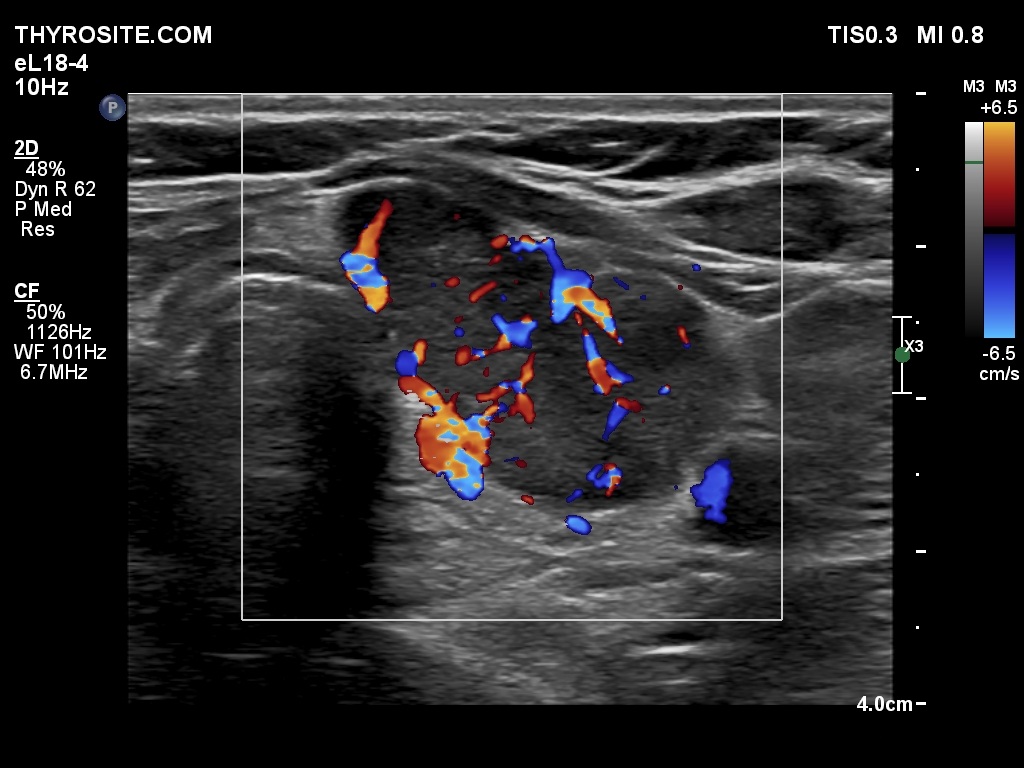

One year after surgery (third row of images)

Ultrasonography: There was no parenchyma according to the right lobe, while there was a relatively large thyroid tissue in the left lobe. The latter displayed increased vascularization.

Three years after surgery (fourth row of images)

Results of blood test: TSH 0.001 mIU/L, FT4 31.9 pM/L, TSAb 9.1 U/L (normal value below 1.5).

Ultrasonography: The pattern remained unchanged.